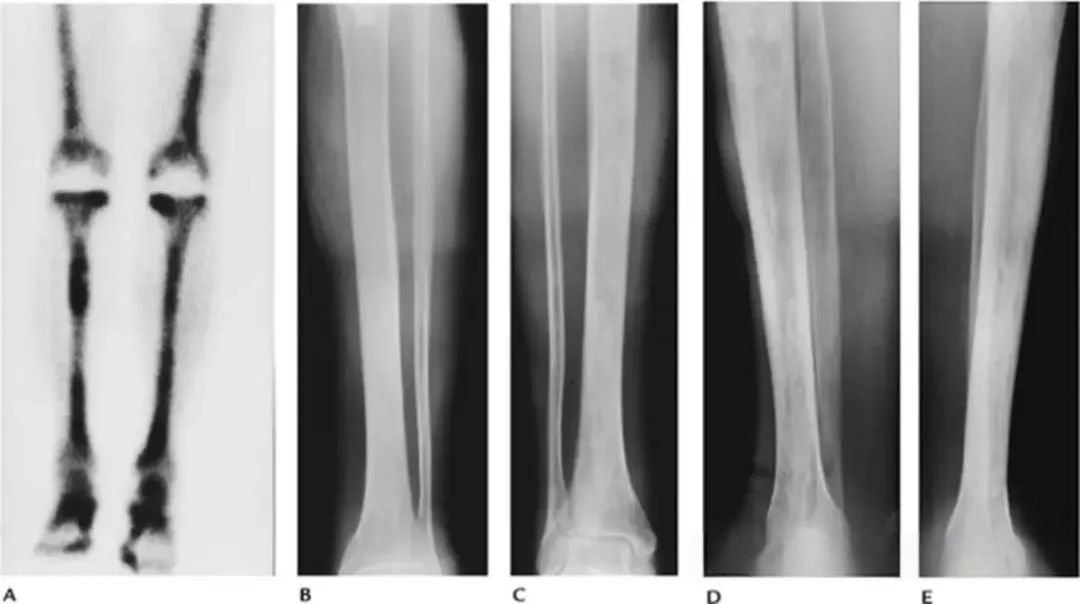

8fab3f42a36ed0ba9f8bae1f62c276ab.jpg

图-9Erdheim-Chester病。放射性核素骨扫描显示双侧股骨和胫骨的示踪剂摄取增加。胫骨的前后位(B、C)和侧位(D、E)X光片显示硬化区,骨小梁明显增粗。